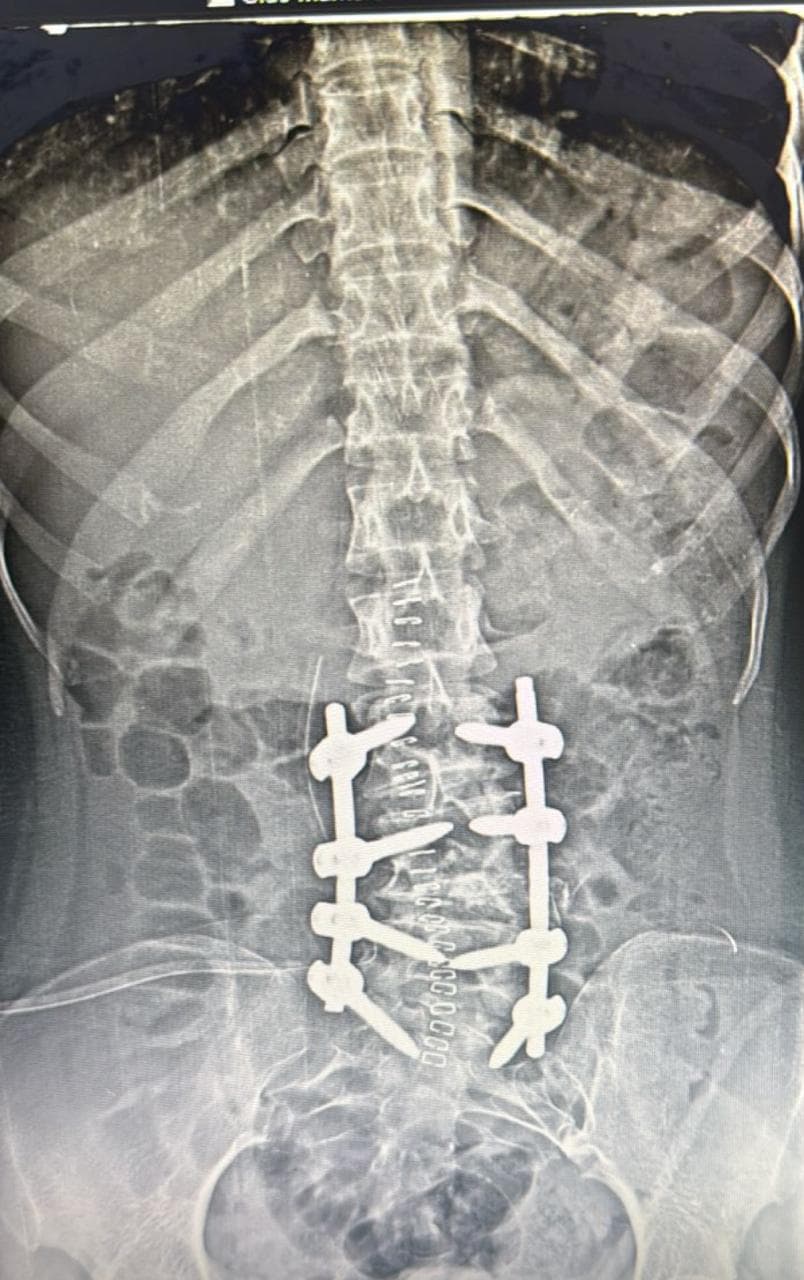

This is the story of a 17-year-old girl who battled congenital scoliosis caused by a hemivertebra at the L4 level, and how timely surgical intervention helped transform her life.

In this patient’s case, the hemivertebra at L4 created a significant lumbosacral curve that affected the natural biomechanics of the spine, causing pain, a tilted posture, and aesthetic concerns.

After thorough evaluation and counseling, Dr. Bhupendra Pratap Bharti , a leading spine deformity correction specialist, recommended surgical correction to prevent further progression of the curve and relieve her symptoms.

The chosen surgical approach was:

This approach was chosen for its effectiveness in correcting deformity while preserving spinal mobility, especially important in a young and active patient.